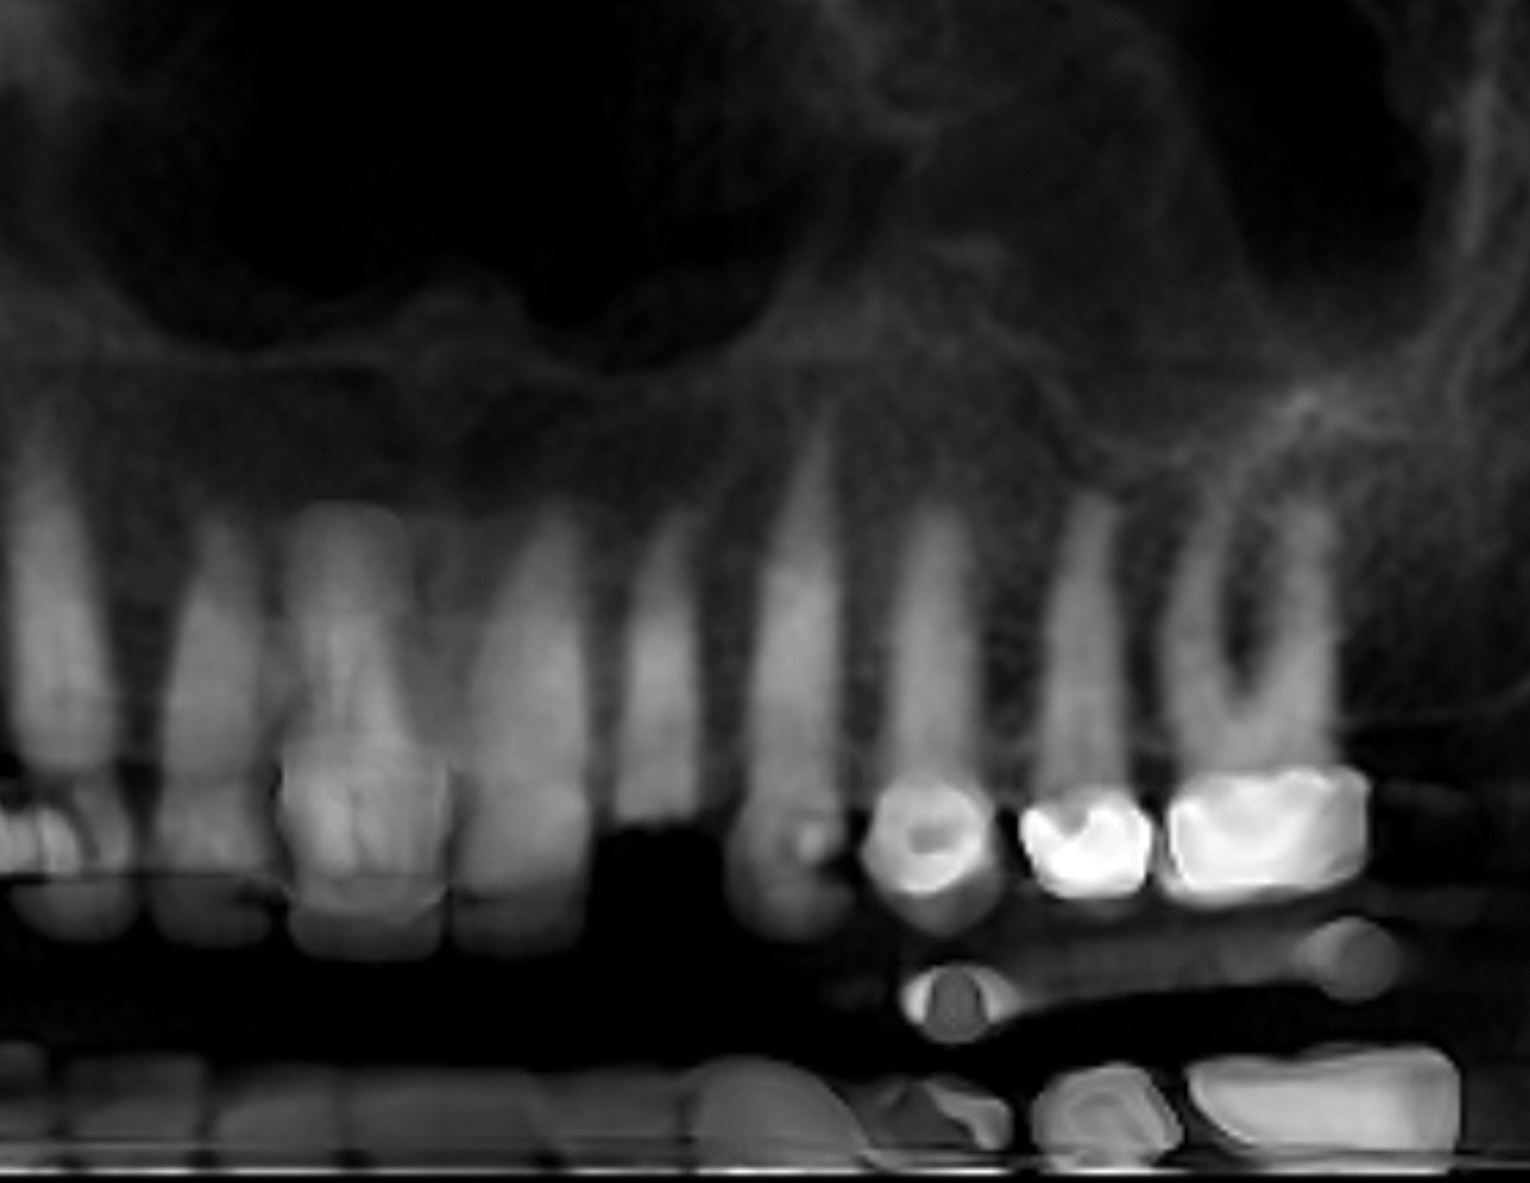

A 68-year-old male patient presented with a failing lower right second molar and retained third molar and was seeking implant restoration at the second molar site (Figure 11 and Figure 12). The patient's medical history was significant for hypertension and cardiac arrhythmia under good control.

After clinical evaluation, CBCT assessment with a dynamic navigation fiducial was followed by planning for immediate implant placement. This included evaluation of inferior alveolar nerve position, undercut, buccal plate dehiscence, implant positioning in the defect, and retention screw path. The patient was taken to surgery under intravenous and local anesthesia with removal of the mandibular right second and third molar teeth. The sites were aggressively debrided with a mesiobuccal root dehiscence noted, and site development followed with the use of dynamic navigation (Figure 13).

Fig 12. Preoperative CBCT-reconstructed radiograph.

Figure 12